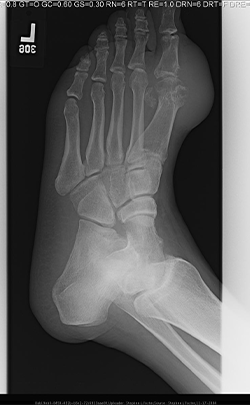

• Se solicitó una radiografía oblicua del pie izquierdo con datos de erosión severa de la cabeza del primer metatarsiano, saliente del margen óseo, tofo suprayacente, ausencia de estrechamiento significativo del espacio articular.